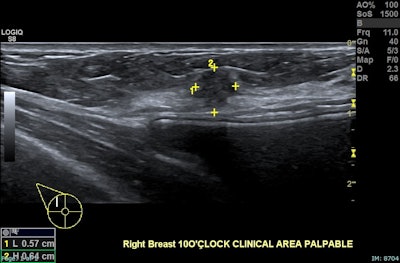

Right breast, 10 o’clock position, same patient: A 15 mm irregular hypoechoic solid lesion with suspicious morphology, situated approximately 6 mm from the index lesion. Biopsy confirmed invasive ductal carcinoma, Grade 2, ER positive, PR positive, HER2 positive, concordant with ultrasound features. Findings are in keeping with multifocal invasive ductal carcinoma in a heterogeneously dense breast. The patient was referred for surgical management.